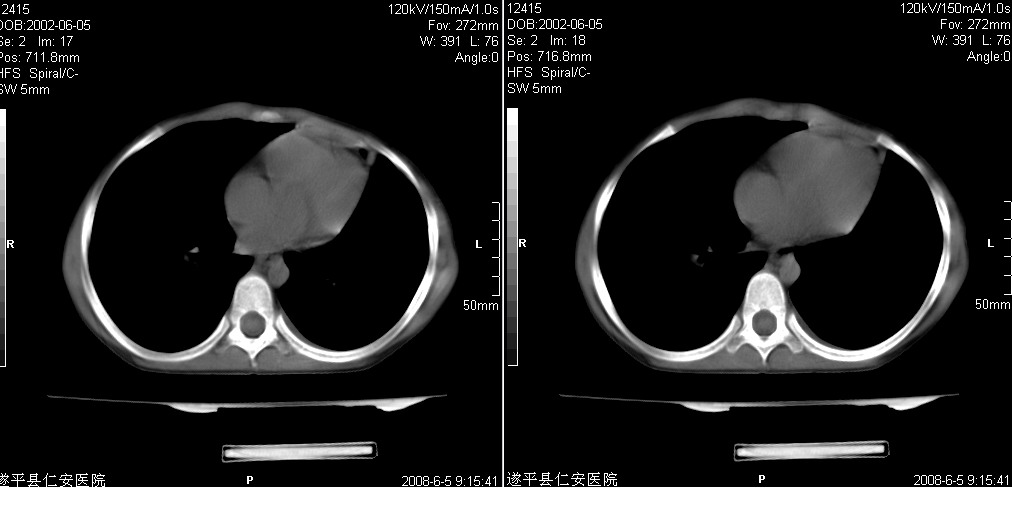

以下是引用xxhwh在2008-6-10 18:40:00的发言:[br]男,6岁,无规则发热一月余,体温在37.8——39度之间。一月前拍胸片示左上肺密度增高影,进行抗炎治疗8天,复查胸片未明显吸收。又改变抗菌素继续治疗半月,照胸片示病灶吸收不明显,行ct检查[br]征象:左上肺前段呈密实影,内可见支气管气像,远侧见絮状模糊影,中上纵隔左移。[br]意见:左上肺前段膨胀不全及感染,考虑为支气管异物或支气管内膜结核所致,[br]建议追问有无异物吸入史,行痰检及ppd检查